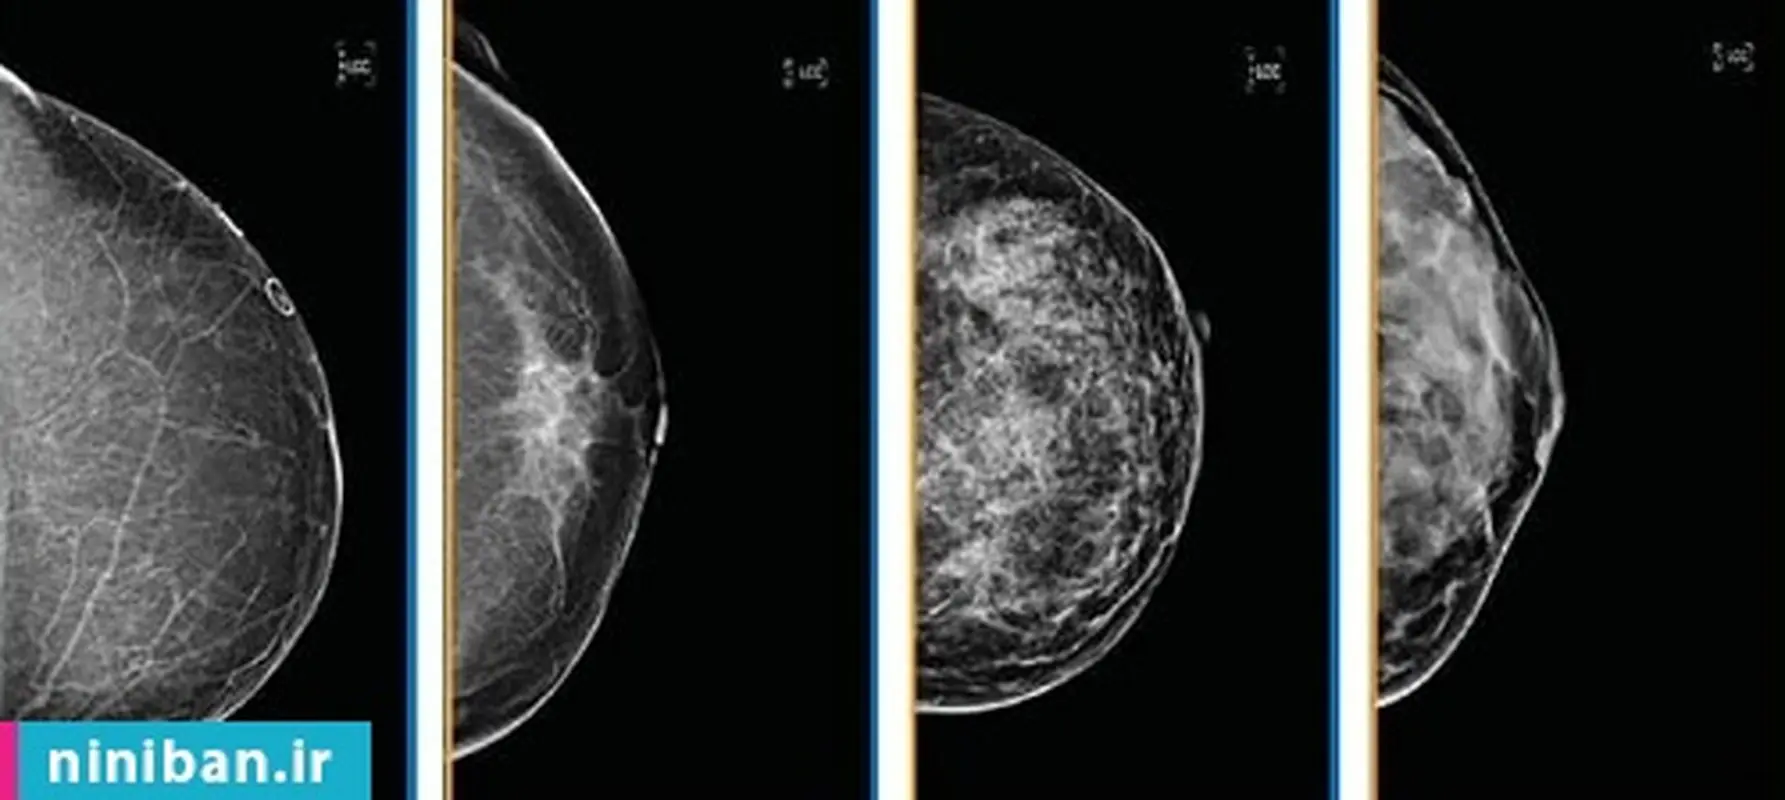

ماموگرافی یکی از بهترین روشهای موجود برای تشخیص زودهنگام است. اما متاسفانه فیزیولوژی انسان، تشخیص یا تفسیر برخی از ناهنجاریها و ضایعات را از طریق ماموگرافی دشوار میکند. مخصوصاً اینکه سینههای متراکم با مقدار زیادی بافت غدهای و همبند میتوانند نگرانیهای بالقوه را پنهان کنند.